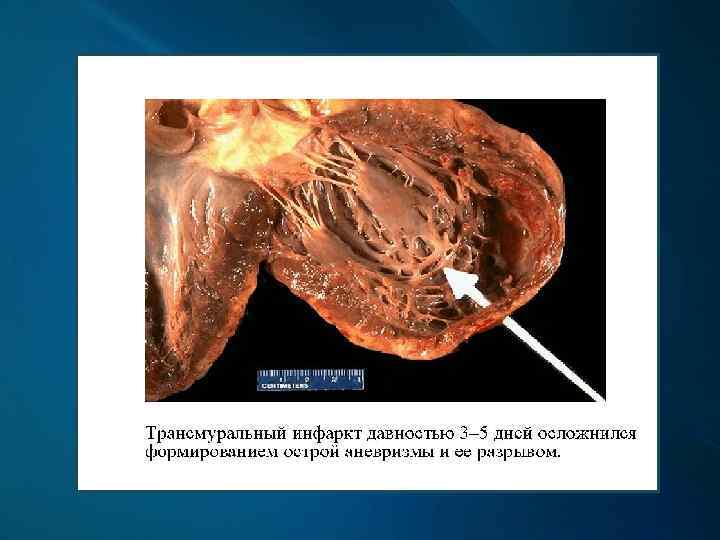

Макроскопически: первые часы - миокард дряблый, неравномерно кровенаполнен; через 18 -24 ч. – четко виден некроз; конец 1 -х сут. – некроз глинистокрасноватый, выбухает из-за отека, с геморрагическим венчиком; к 4 -6 сут. и далее – некроз западает, плотный, желто-серый, с красной каймой грануляционной ткани вокруг; через 3 -5 нед. – рубец красновато-серый, затем белесовато-серый.

Гемотампонада перикарда при разрыве стенки желудочка сердца

Макропрепарат сердца: постинфарктный кардиосклероз

Хроническая постинфарктная аневризма сердца

Хроническая постинфарктная аневризма сердца